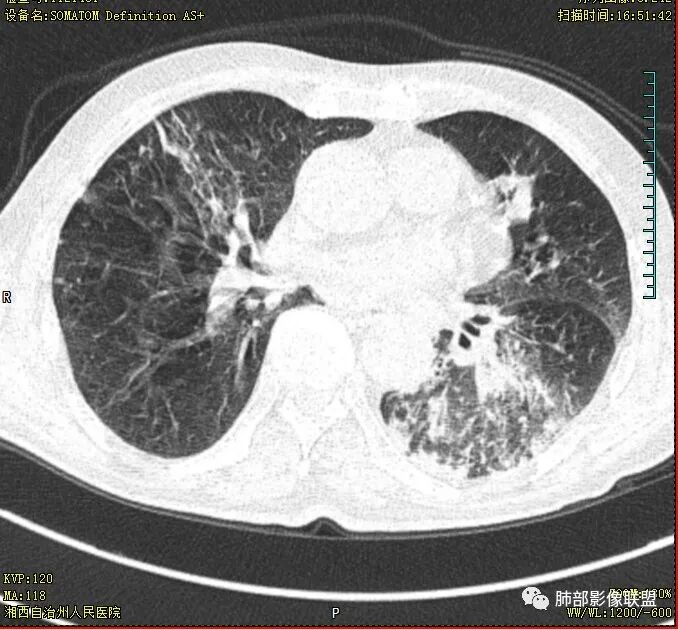

晨读:老年男性患者,痰中带血伴间断发热2周,体温39.4℃,白细胞、中性粒细胞,CRP增高,Tspot阳性,胸部CT:双肺病变,左肺下叶背段大片实变密度影,边界模糊,内部见空洞形成,空洞内壁总体光滑,有气液平,增强扫描轻度不均匀强化,一月后复查空洞消失,实变影吸收减少,考虑感染性病变,结核伴肺脓肿。

晨读,老年男性,中等病程,咳嗽,痰中带血,发热,主病灶位于左肺下叶空洞,厚壁,偏心,内壁光滑,边界清楚,不均匀强化,内有坏死,考虑结核,内有气液平,周围部分小叶中心结界,好热,白细胞升高,合并感染。结核合并感染,鉴别肺癌合并感染。

老年慢性长期吸烟,痰中带血伴发高热。左下肺大片不均质实变里可见一含气液平厚壁空洞,内壁有坏死物残留,增强可空洞壁明显强化轮廓显示清晰,空洞位于肺门侧,近端支气管壁不规则增厚。两肺散在斑片状影,并见小树芽。18号复查肺窗空洞显示不清,20号用了俯卧位扫描,液体向下流动空洞又显示出来了。左下肺病灶有变小,还是考虑感染性病变,结核合并感染,鉴别鳞癌。

老年患者。左肺下叶厚壁空洞,有液平面。空洞内壁较为光整。病灶的内侧见支气管节段性的变窄扭曲。两肺内,弥漫性的广泛性的播散病灶。考虑感染性病变。肺结核并空洞形成两肺内播散。鉴别诊断-左肺下叶鳞癌。

双肺多发结节影,树芽征,小叶中心分布,左肺下叶不规则空洞,洞内壁光滑,见液平,洞壁似与支气管相通,增强扫描明显强化,可见血管造影征。三周左右复查空洞明显缩小。

双肺多发点片、索条斑条灶,见多发树丫征,左下肺大片不均质实变,内见一含气液平厚壁空洞,壁厚,内壁有坏死物残留,增强可空洞壁明显强化

,空洞位于肺门侧,近端支气管壁不规则增厚。

胸部CT:双肺多发小斑片、树芽、索条灶,左下肺大片不均质实变,远肺门侧厚壁空洞,气液平,内壁有坏死物残留,增强可空洞壁不均匀强化,近端支气管壁不规则增厚堵塞,实变影内可见与洞壁平行支气管。抗炎3周有缩小。

双肺边界较清楚的斑点状影、树芽征,结合T-SPOT阳性,长病程,体重减轻等,继发性肺结核是应当考虑的,至少作为基础疾病之一。

3.注意到左肺下叶空洞性病灶,腔壁厚度不均,环形强化较为明显,壁间支气管血管影走行,腔内液气平面,这通常见于感染性病灶,如脓肿,经治疗病灶吸收也高度支持病灶主体成分为脓肿。